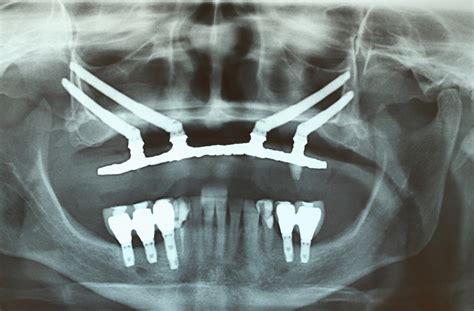

- Evaluación inicial y diagnóstico: El primer paso es una evaluación detallada del paciente, que incluye una revisión de su historial médico, un examen clínico y pruebas radiográficas, como tomografías computarizadas (CBCT), para evaluar la cantidad y calidad del hueso disponible.

- Planificación quirúrgica: Una vez que se determina el estado del hueso y las características específicas del paciente, el cirujano implantólogo planifica la ubicación de los implantes. Esta fase es crucial para garantizar que los implantes se coloquen en las posiciones más adecuadas para soportar la prótesis.

- Procedimiento de colocación de los implantes: Durante la cirugía, los implantes se insertan en el hueso maxilar o mandibular bajo anestesia local o sedación. Dependiendo del tipo de implante y la condición del paciente, la colocación de una prótesis provisional puede realizarse el mismo día o después de un periodo de osteointegración, que suele durar entre 3 a 6 meses.

En cambio, en las piezas dentales definitivas no se aprecia tan fácilmente. Sin embargo, hay un signo que nos puede hacer sospechar la agenesia: un diente de leche que tarda en caerse más de lo habitual. Por ello, para poder diagnosticar la agenesia en dientes definitivos es necesario realizar una radiografía panorámica, que ofrezca una vista completa de las dos arcadas dentarias (superior e inferior).